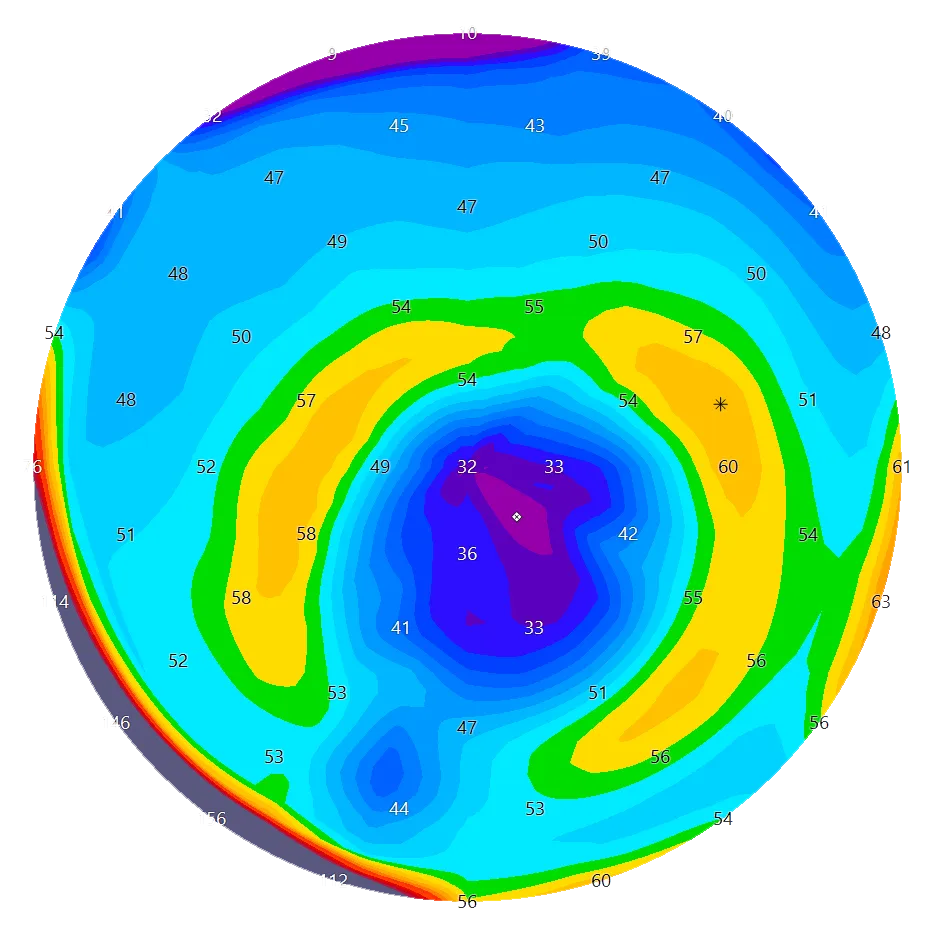

Diese Hornhaut ist erkrankt und benötigt weitere Untersuchungen/Behandlungen. Man erkennt, dass die Hornhaut im oberen Anteil flach ist und im unteren Anteil sehr stark vorgewölbt. Die Sehkraft ist verzerrt, es bestehen Doppel- oder sogar Dreifach- und Vierfach-Bilder und in vielen Fällen kann auch eine Brille die Sehschärfe nicht mehr wiederherstellen. Zudem ist die Krankheit fortschreitend und kann vor allem bei Kindern und Jugendlichen bis zu schwersten Sehbehinderungen führen.

Das MS-39 kombiniert Hornhauttopographie mit hochauflösender OCT (optische Kohärenztomographie). Es liefert uns ein extrem detailliertes Bild der Hornhautschichten, mit dem wir subtile strukturelle Veränderungen erkennen und ein Fortschreiten im Laufe der Zeit überwachen können.

Dank neuester Technologien sind wir heute in der Lage, sowohl die vordere als auch die hintere Oberfläche der Hornhaut mit extrem hoher Präzision zu messen. Dank dieser verbesserten Genauigkeit können Anomalien bereits in sehr frühen Stadien erkannt werden, was zu schnelleren und zuverlässigeren Diagnosen führt. Erkrankungen wie Keratokonus oder Pellucid Marginal Degeneration (PMD) lassen sich nun deutlich früher als bisher diagnostizieren, was die Patientenergebnisse verbessert und eine rechtzeitige Behandlung ermöglicht.

Die moderne OCT-Technologie für den vorderen Augenabschnitt bietet eine ultrahochauflösende Darstellung des Hornhautgewebes und ermöglicht eine unglaublich detaillierte Visualisierung seiner Struktur. Dieses Mass an Präzision ist ein grosser Vorteil bei der Nachsorge von Hornhauterkrankungen und der postoperativen Überwachung. Sie ermöglicht es den Ärzten, subtile Veränderungen der Hornhaut im Laufe der Zeit mit grosser Genauigkeit zu verfolgen.

Einer der wichtigsten Vorteile dieser Bildgebung ist die Möglichkeit, Hornhautnarben nicht nur hinsichtlich ihres Vorhandenseins, sondern auch ihrer Tiefe und Ausdehnung innerhalb der Hornhautschichten zu beurteilen. Solche detaillierten Informationen sind entscheidend für die Bewertung der Auswirkungen auf die Sehqualität und für die Planung künftiger Behandlungsstrategien, falls erforderlich.